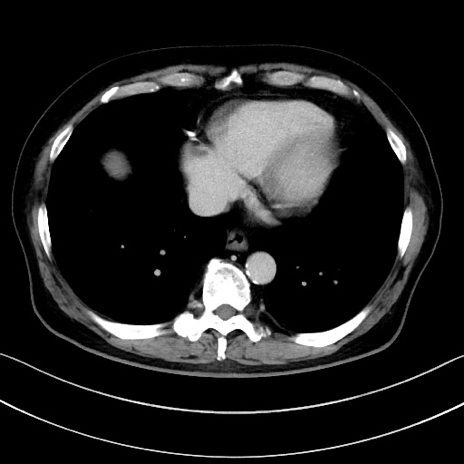

症例15(横断像)

【症例】70歳代男性

【主訴】腹痛

【現病歴】今朝から腹痛あり。全体的に痛い。特に左上の方。排ガスが今日はない。冷や汗が出る。

【既往歴】直腸癌術後

【身体所見】左側腹部〜上腹部に圧痛あり。腹膜刺激症状明らかなではない。軽度反跳痛。左下腹部に術後瘢痕あり。

【データ】WBC 7700、CRP 0.02